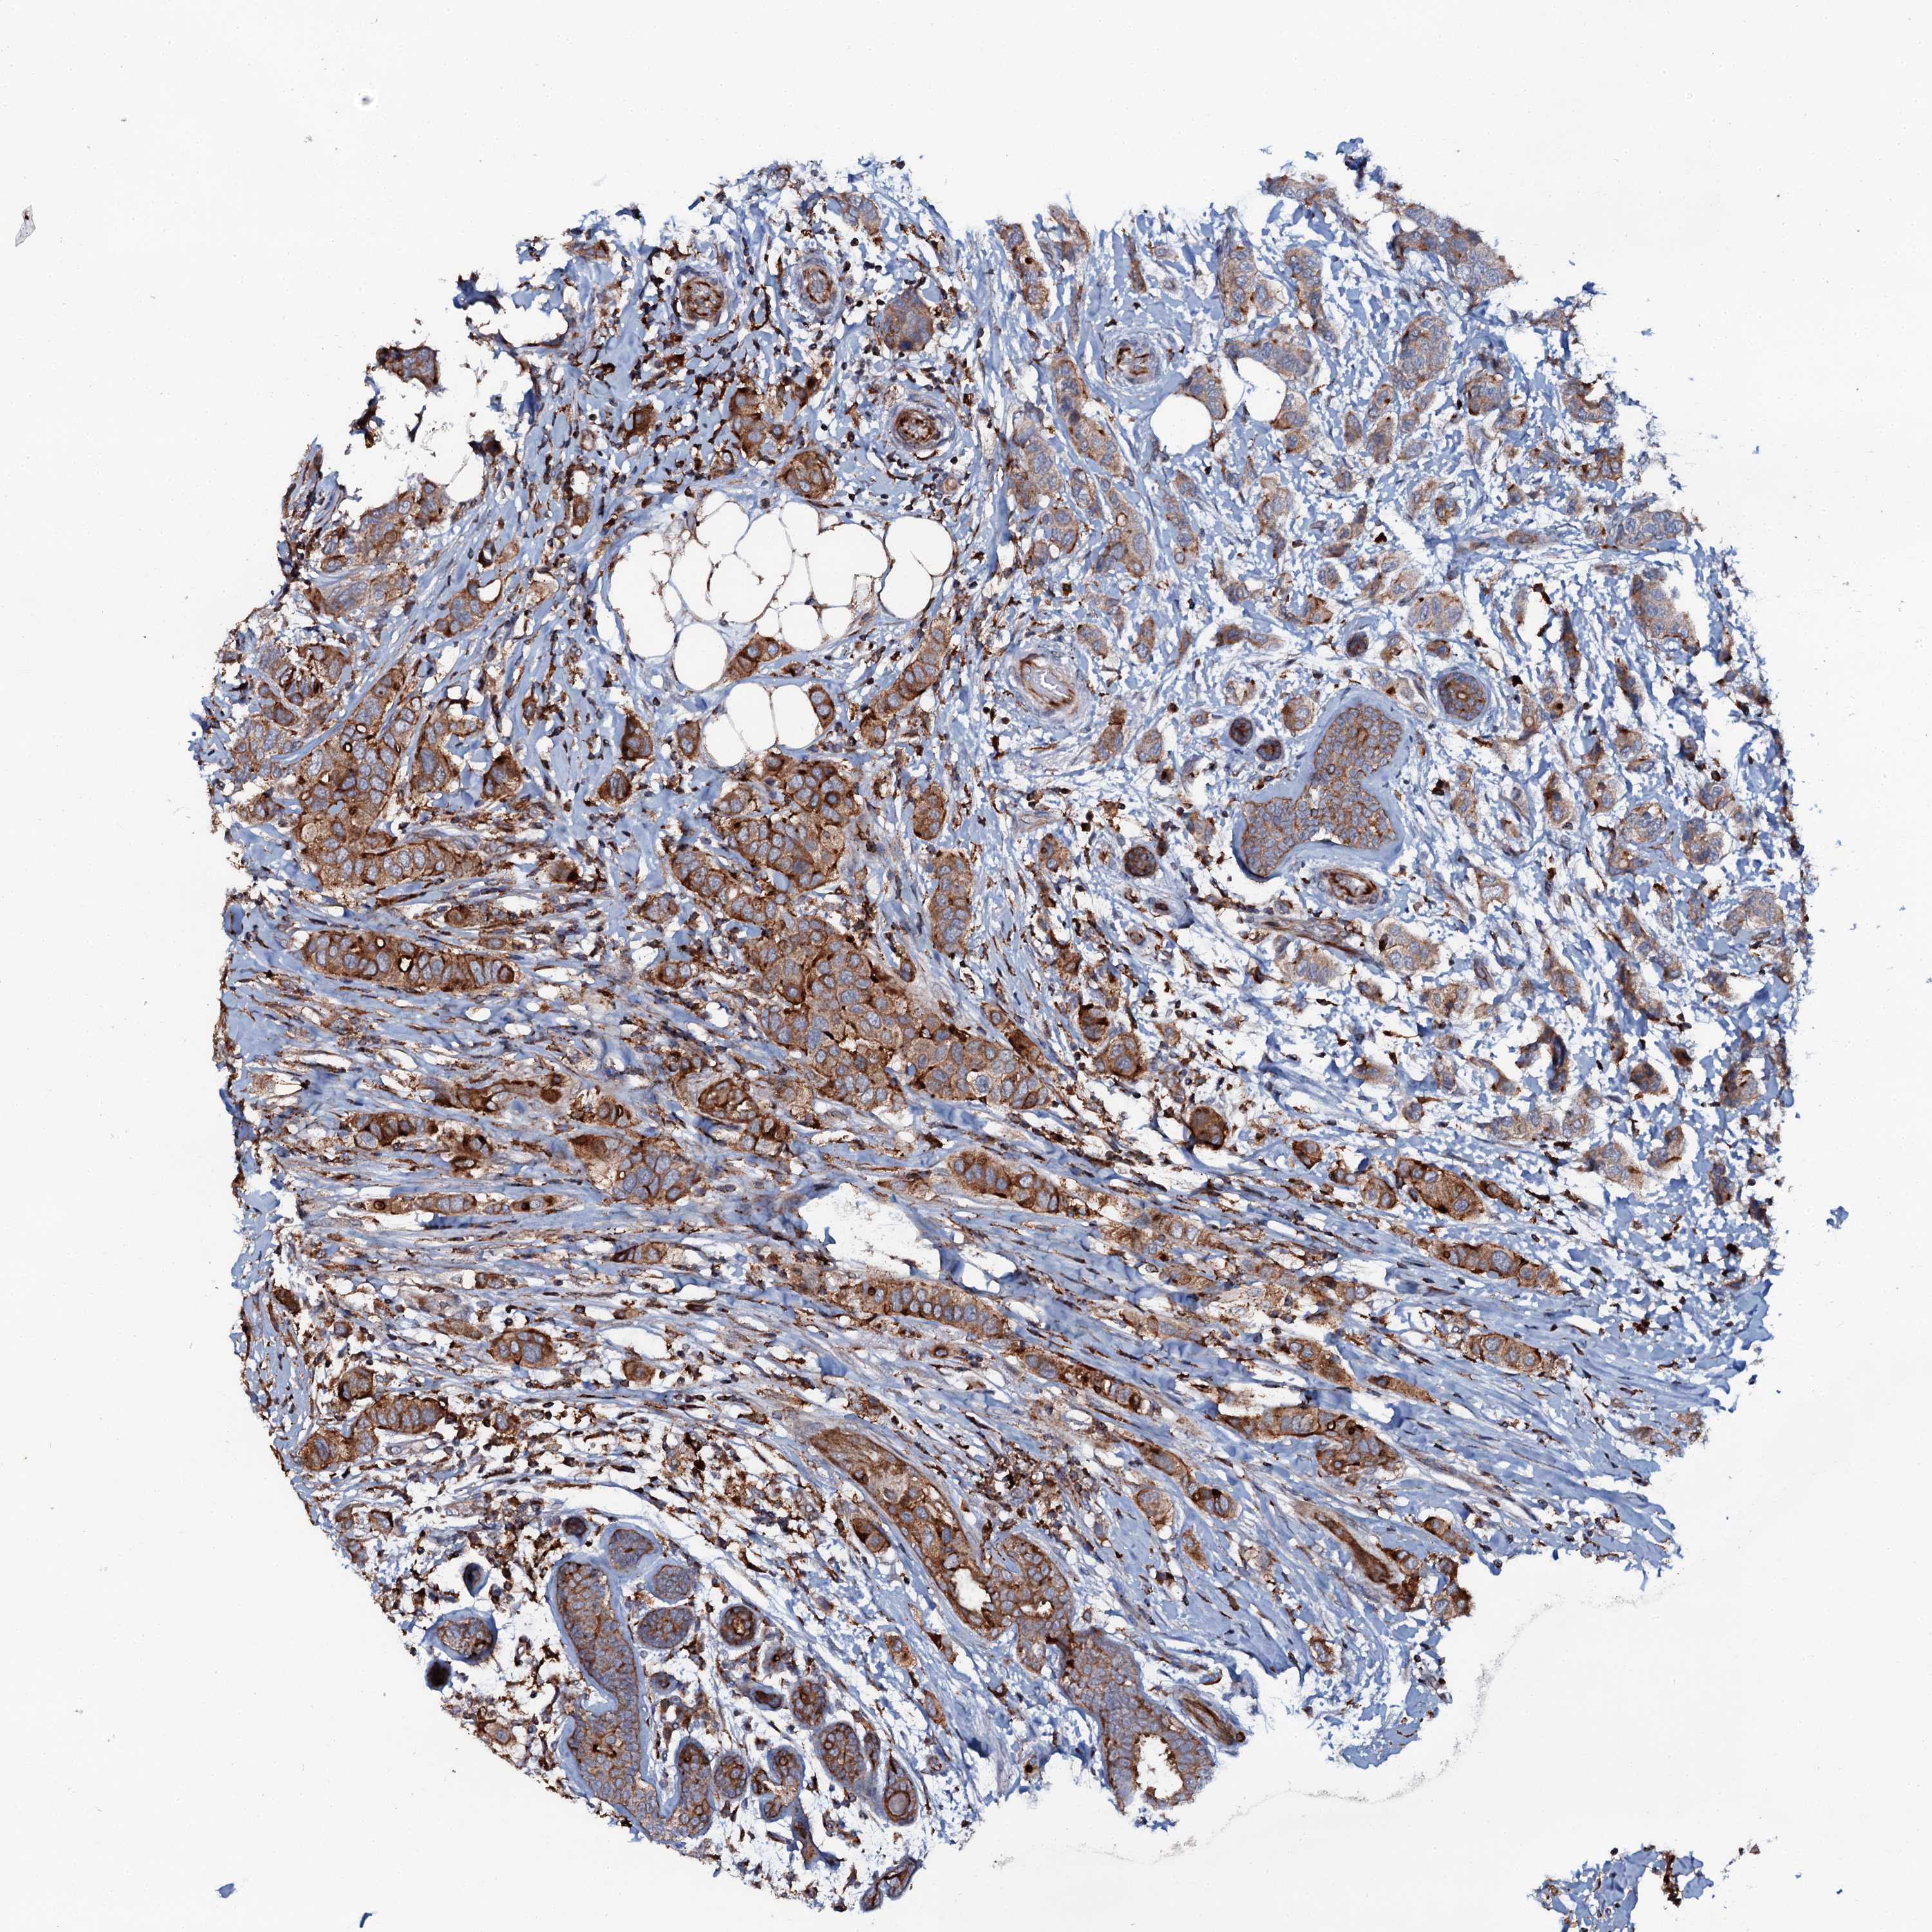

CANCER BREAST CANCER Show tissue menu

BRCA TCGA BRCA VALIDATION PROTEIN EXPRESSION